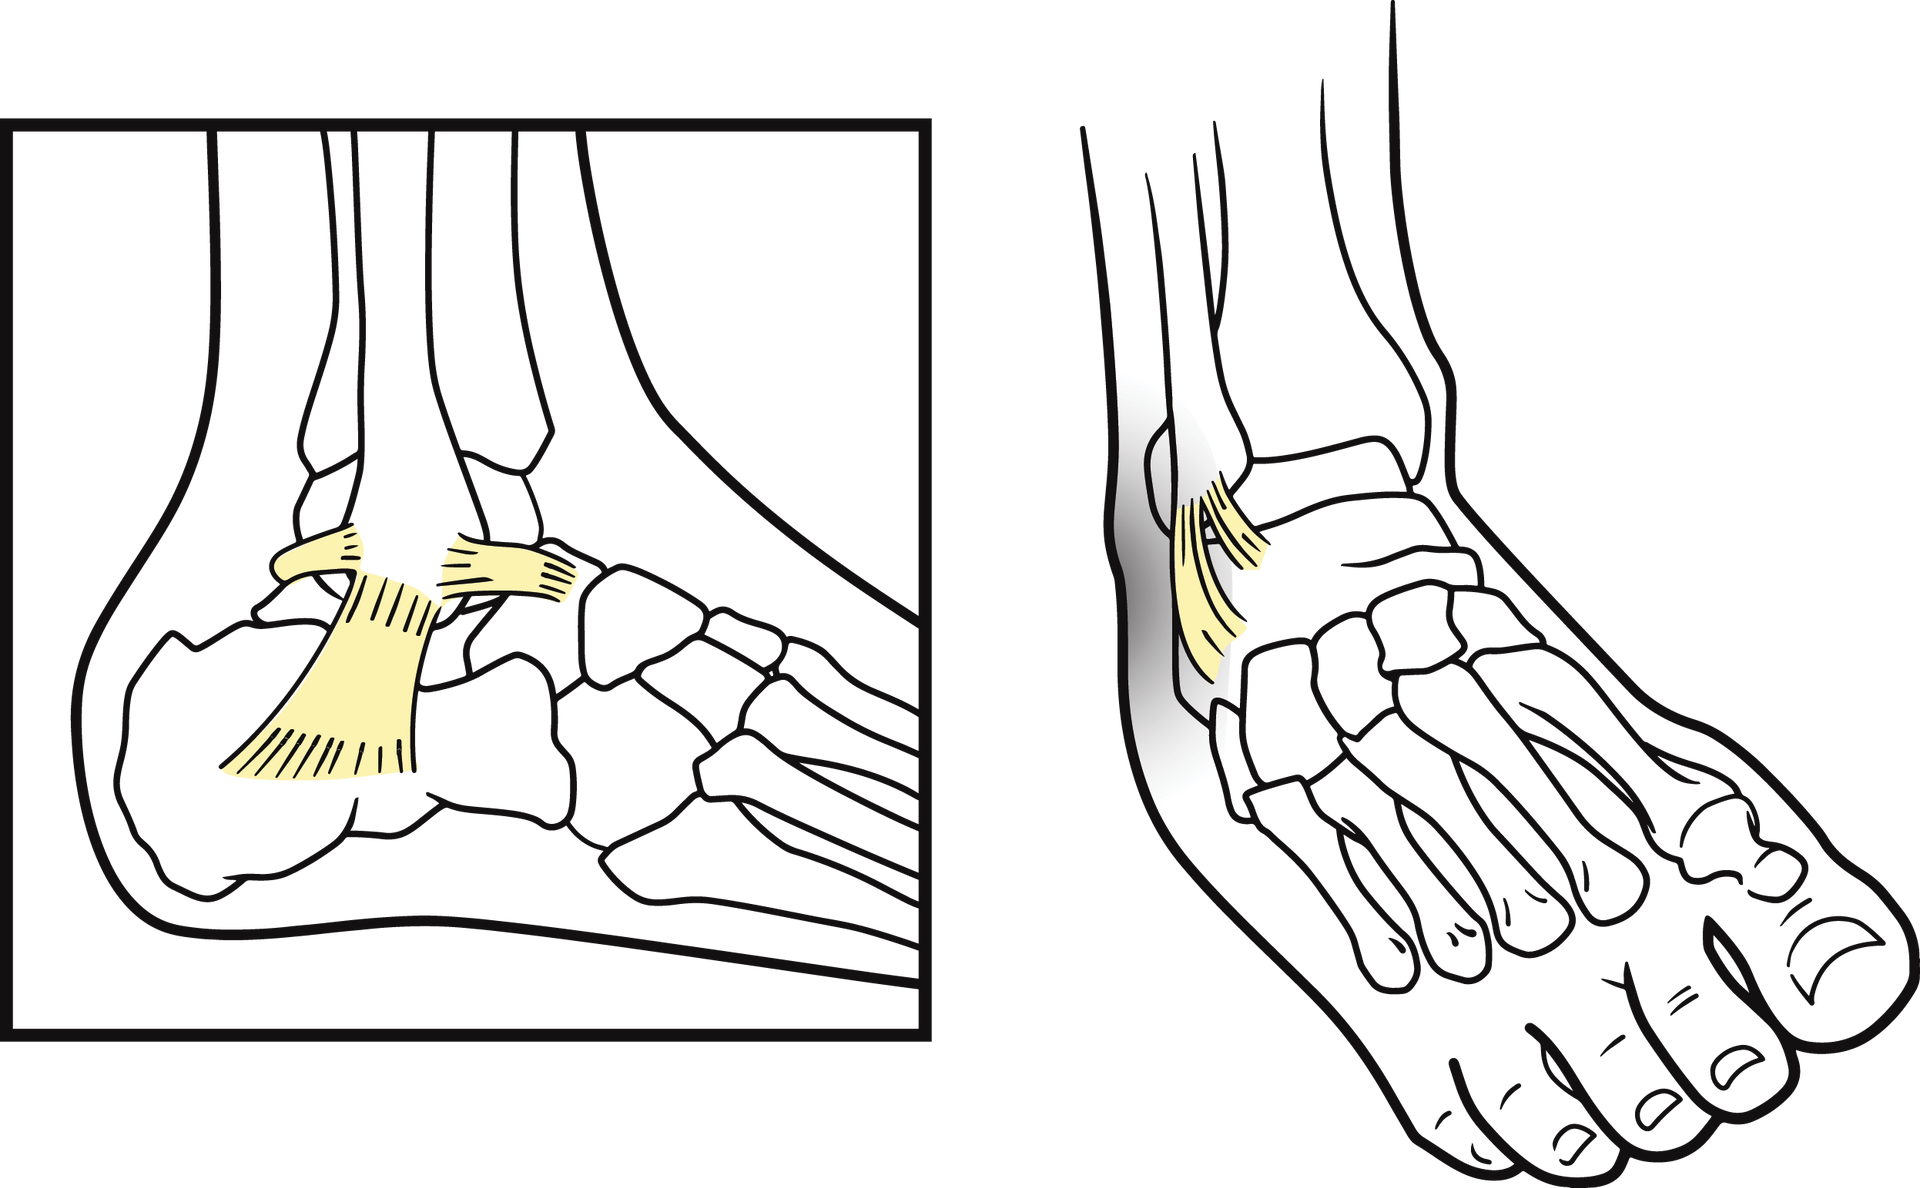

Tout d’abord, nous allons vous expliquer à quoi correspond un ligament et son rôle. C’est en effet cette structure qui est mise en tension lors de la survenue de l’entorse.

Les ligaments sont des structures fibreuses, peu extensibles, qui relient deux os entre eux au niveau d’une articulation. Ils sont donc présents au niveau de la cheville, du genou, du coude ou de l’épaule par exemple.

Le ligament permet de protéger les articulations de mouvements excessifs, dangereux. Il permet de maintenir l’articulation dans une position physiologique en limitant l’amplitude du mouvement.

Mais cette structure peut être soumise à des blessures, c’est l’entorse. Elle est fréquente au niveau de la cheville ou du genou et se traduit par un œdème (gonflement) et un possible craquement sec dans les cas les plus graves. La zone en question sera également chaude, douloureuse, rouge voire violette si un hématome survient.

L’entorse correspond à une distension du ligament trop importante dépassant la capacité de résistance du ligament. Le ligament sera alors seulement distendu ou bien rompu lors d’une entorse grave.